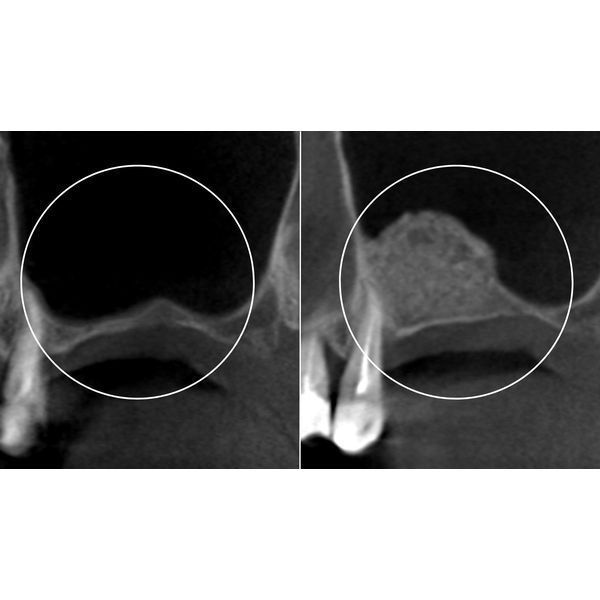

Женщине провели 3D-диагностику, чтобы оценить состояние твёрдых тканей в месте будущей имплантации.

До установки импланта нужно было провести остеопластику, а именно синус-лифтинг. Из-за долгого отсутствия зуба и атрофии кости выбран открытый тип процедуры, который позволяет быстро и надёжно восполнить костную ткань.

Во время синус-лифтинга пациентке под анестезией разрезали десну, просверлили отверстие в боковой стенке гайморовой пазухи и ввели в это «окошко» специальный материал для восстановления объёма костной ткани. Открытый синус-лифтинг предполагает отсроченную установку имплантов, поэтому после операции женщине наложили швы и отпустили её домой.

После открытого синус-лифтинга обычно кость восстанавливается в среднем за 3–6 месяцев. В данном случае костный материал успешно прижился за полгода. Весь этот период пациентка наблюдалась у врача для контроля состояния.